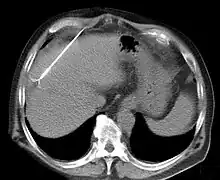

TC que muestra la ablación por radiofrecuencia de una lesión hepática.

La ablación basada en energía busca la destrucción de una pequeña parte del tejido mediante la aplicación controlada de energía, tal como corrientes de radiofrecuencia (RF), microondas, láser, ultrasonidos, aplicación de pulsos de alto voltaje (electroporación), etc. Existen muchos objetivos clínico para esta destrucción del tejido. Por ejemplo, en ablación cardíaca se desea la destrucción de las células cardíacas causantes de una arritmia, mientras que en ablación de tumores, la destrucción debe lograr alcanzar a todo el volumen del tumor más un zona periférica segura.

En la ablación por radiofrecuencia la destrucción se logra por aumento de temperatura debido al paso de la corriente de alta frecuencia (100 kHz-1MHz). Esta corriente no produce estimulación nerviosa ni muscular, sino solo calentamiento. Los procedimientos de ablación por radiofrecuencia se realizan bajo la guía de imágenes (por ejemplo de rayos X, tomografía computarizada o ecografía) por un anestesiólogo, o un radiólogo intervencionista, o un endoscopista gastrointestinal, o un electrofisiólogo cardíaco.